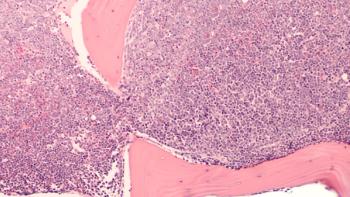

Lymphoma